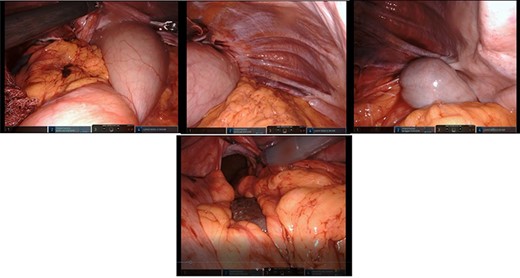

After mobilization of the left liver lobe, visualization of the hiatus was achieved. A two silk suture was placed through the avascular hepatogastric ligament and outside the patient’s anterior abdomen with an extracorporeal knot in order to assure atraumatic elevation-retraction of the liver. Space was created in the surgical field due to the absence of a retracting surgical instrument within the abdominal cavity. The hernia’s sac was then dissected with use of energy device and bipolar cautery with minimal traumatic tissue handling; the herniated stomach, transverse and left colon, omentum and finally spleen were dissected free (Fig. 2). Due to the atypical clinical symptomatology as well as increased PLT, the suspicion of chronic ischemia of the herniated organs was raised. ICG was administered to assess the patency of blood supply in the herniated organs and specially to the spleen; blood supply was excellent and as a result, no further resections were needed (Fig. 3). An 8- × 4-cm posterolateral diaphragmatic defect was revealed; the defect was repaired with the use of ProGrip mesh and was supported by a continuous V-loc suture for fixation. The patient resuscitated from anesthesia in great condition and returned to the ward, with an uneventful course. A post-operative upper GI fluoroscopy was conducted at the second post-operative day (POD), and oral diet was commenced (Fig. 4).

Top left: reduction of the dilated stomach from the hernial sac; retraction of the anterior border of the hiatus; top middle: presence and reduction of omentum from the hernial sac; top right: identification of the large intestine within the Bochdalek hernia; bottom middle: reduction of the spleen and great visualization of the large hiatus.